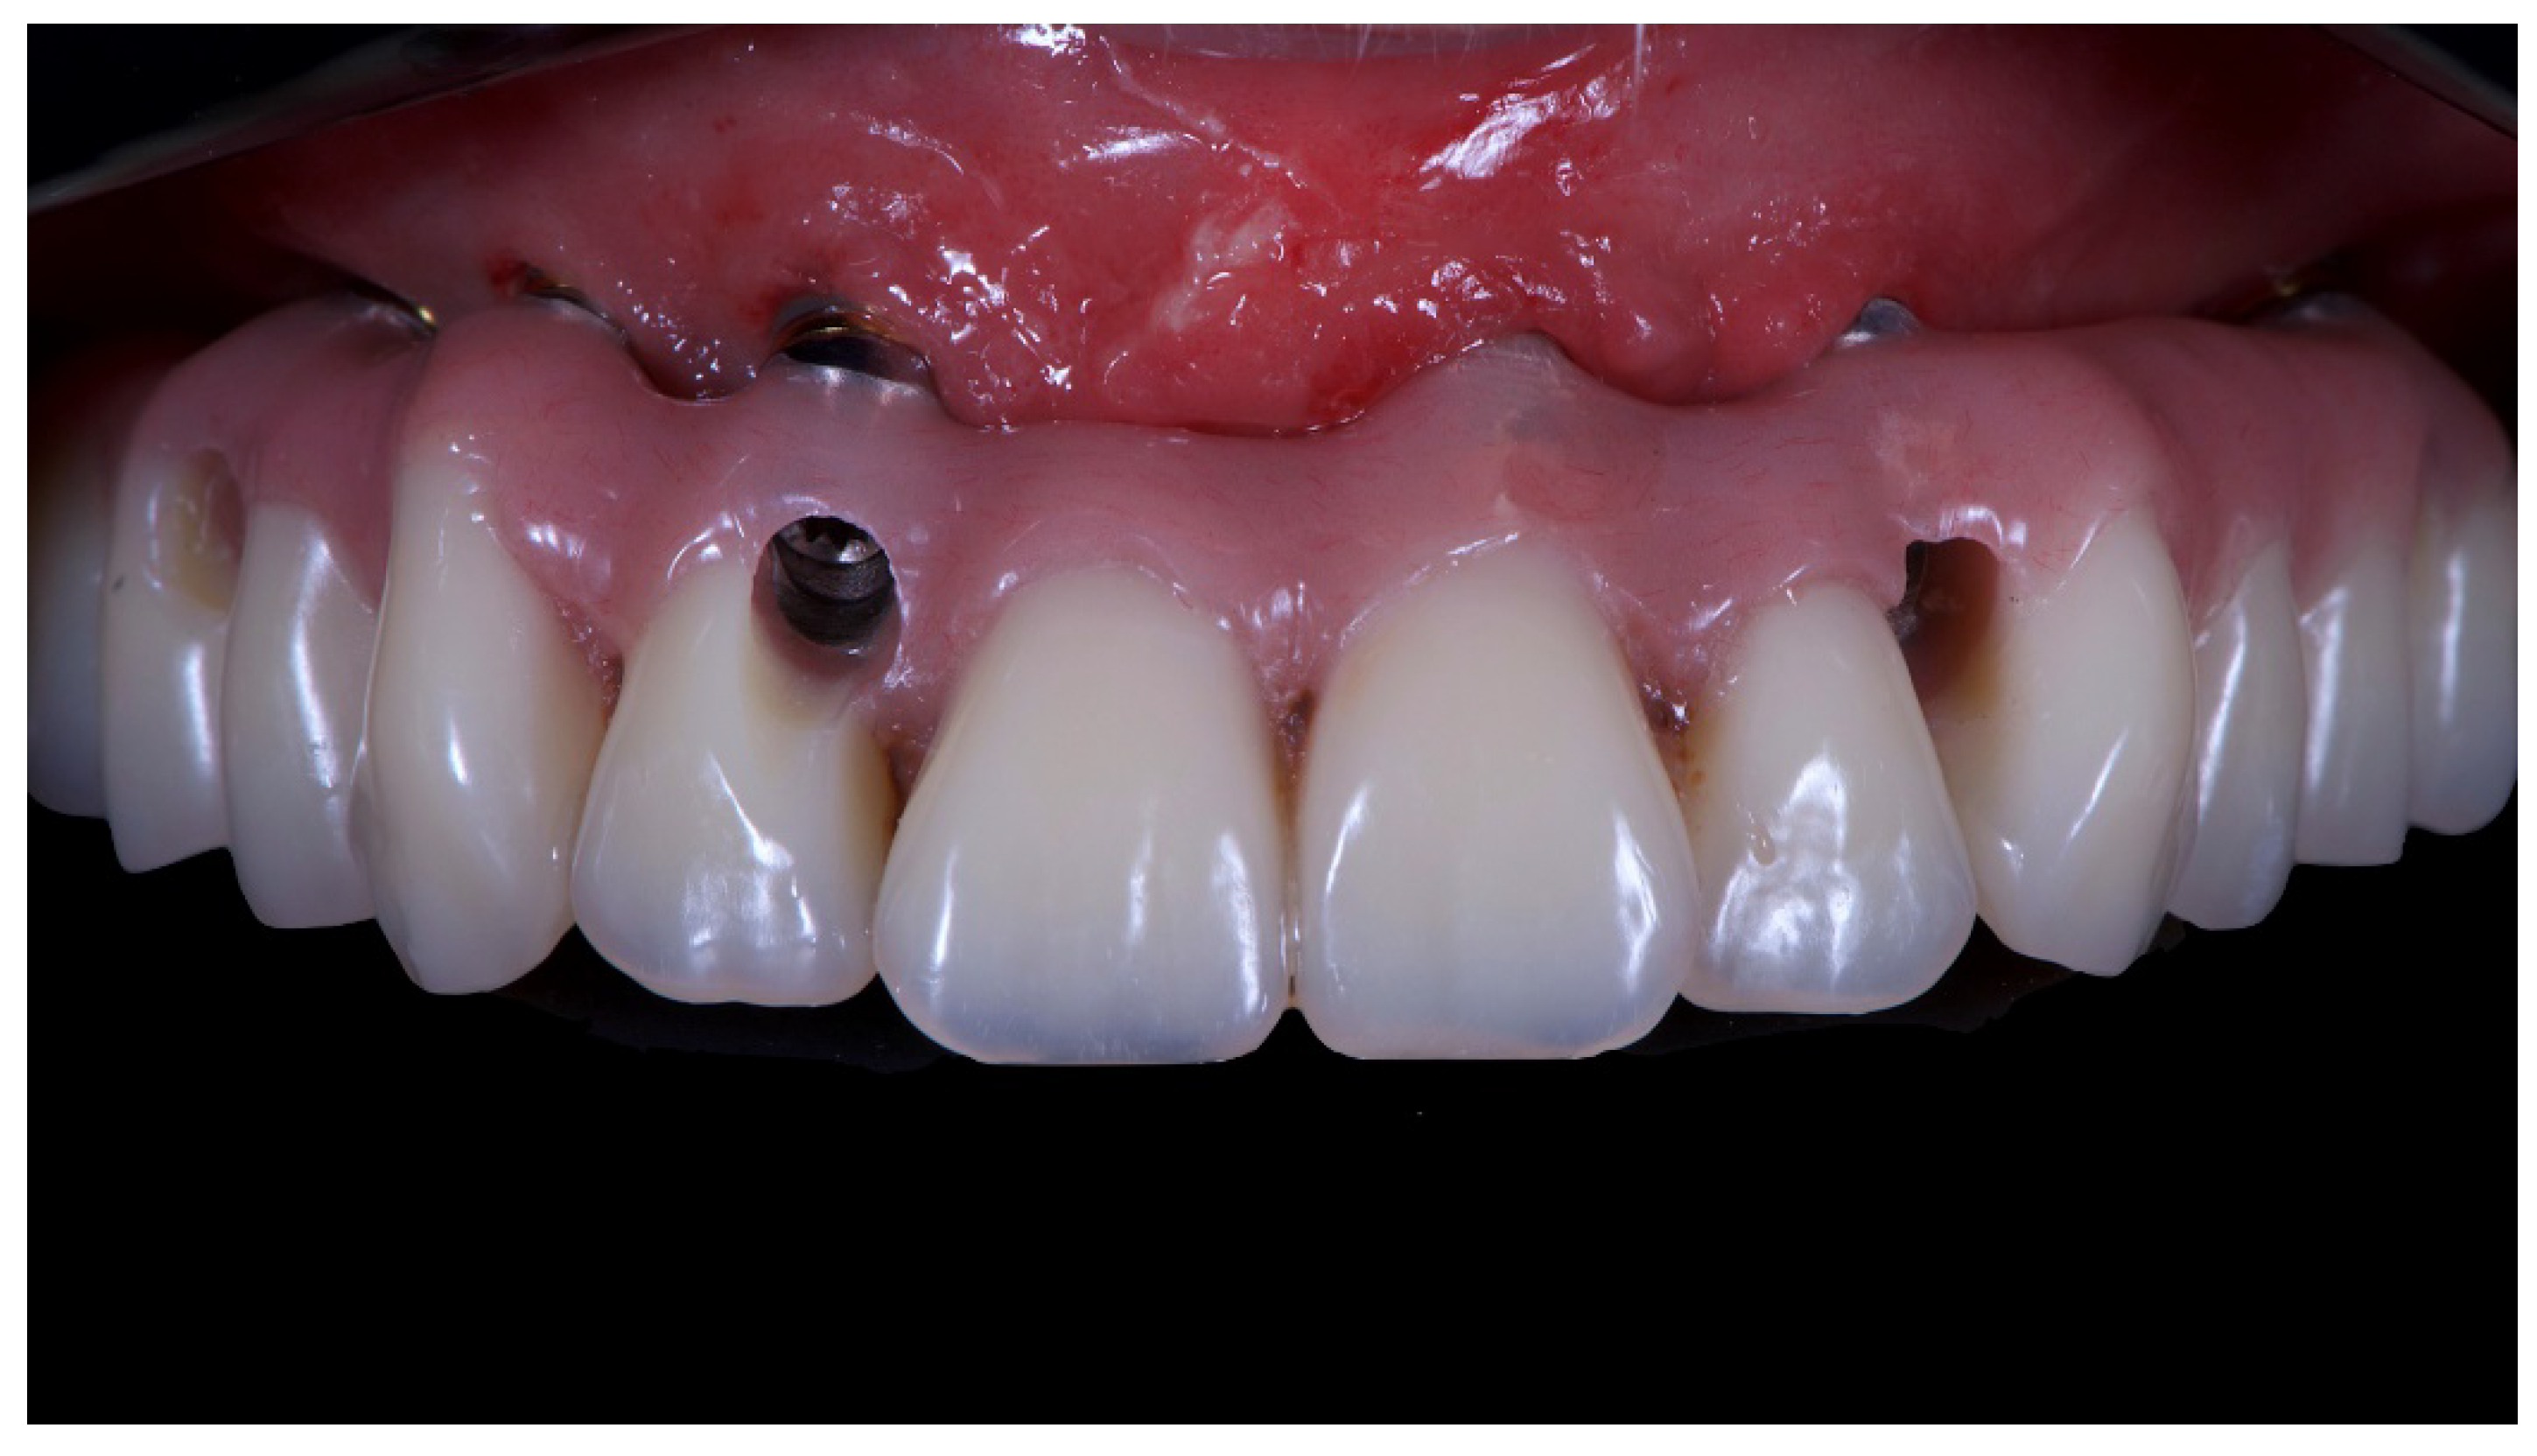

Figure 13.

Final prosthesis mounted. Note the through holes. In two cases, it was compensated with only the Seeger, without a through screw.